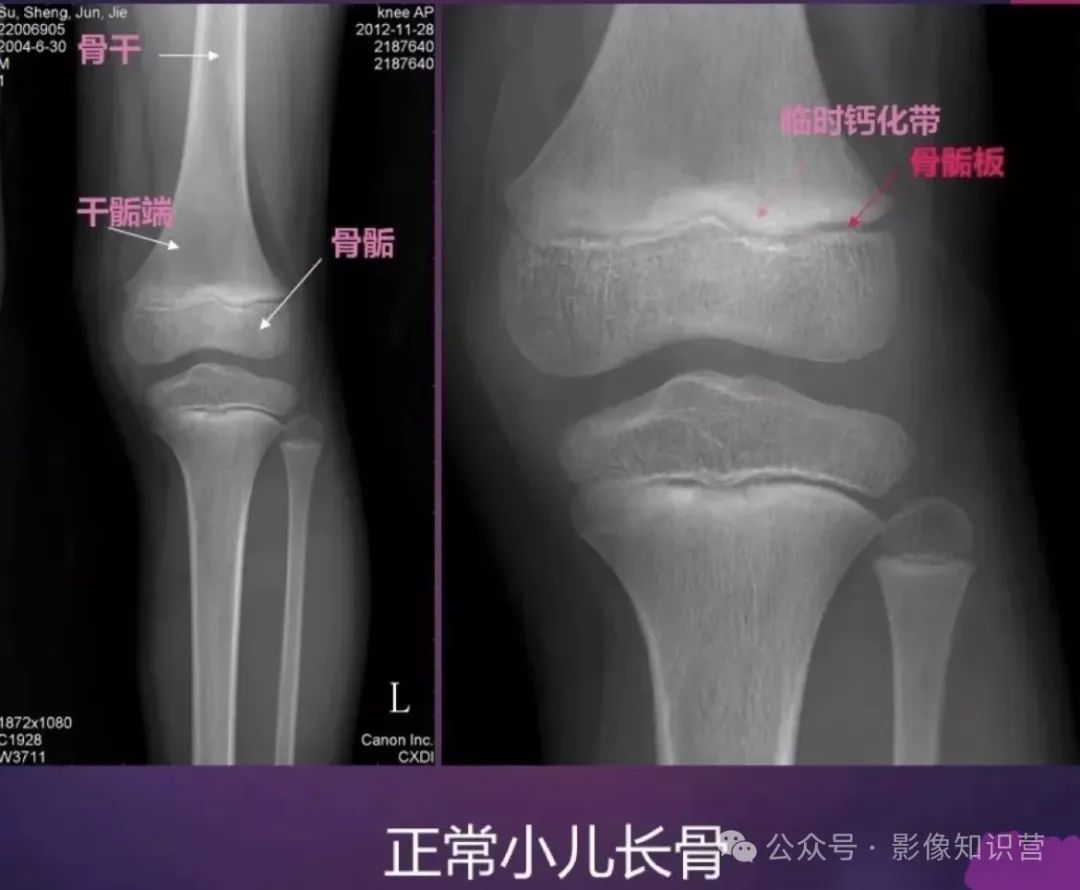

膝关节骨骼组成:股骨远端、胫骨近端、髌骨。

影像特征:X线侧位:观察髌骨位置及关节间隙(正常约3-5mm)。MRI可评估半月板(内“C”形、外“O”形)、交叉韧带及软骨损伤。

胫骨:位于小腿内侧,是小腿主要的负重骨。胫骨上端膨大,有内侧髁和外侧髁,两髁之间有髁间隆起。胫骨体前缘锐利,下端内踝是重要的体表标志。

腓骨:位于小腿外侧,较细。上端为腓骨头,下端为外踝,外踝比内踝略低。